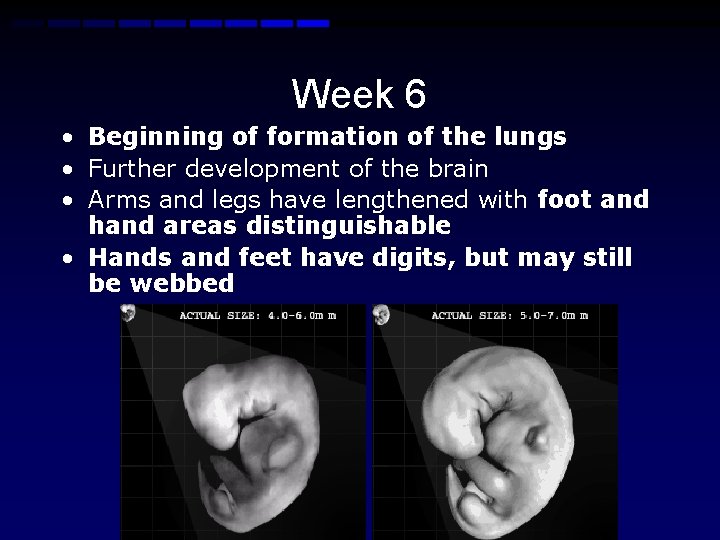

Week 6 • Beginning of formation of the lungs • Further development of the brain • Arms and legs have lengthened with foot and hand areas distinguishable • Hands and feet have digits, but may still be webbed